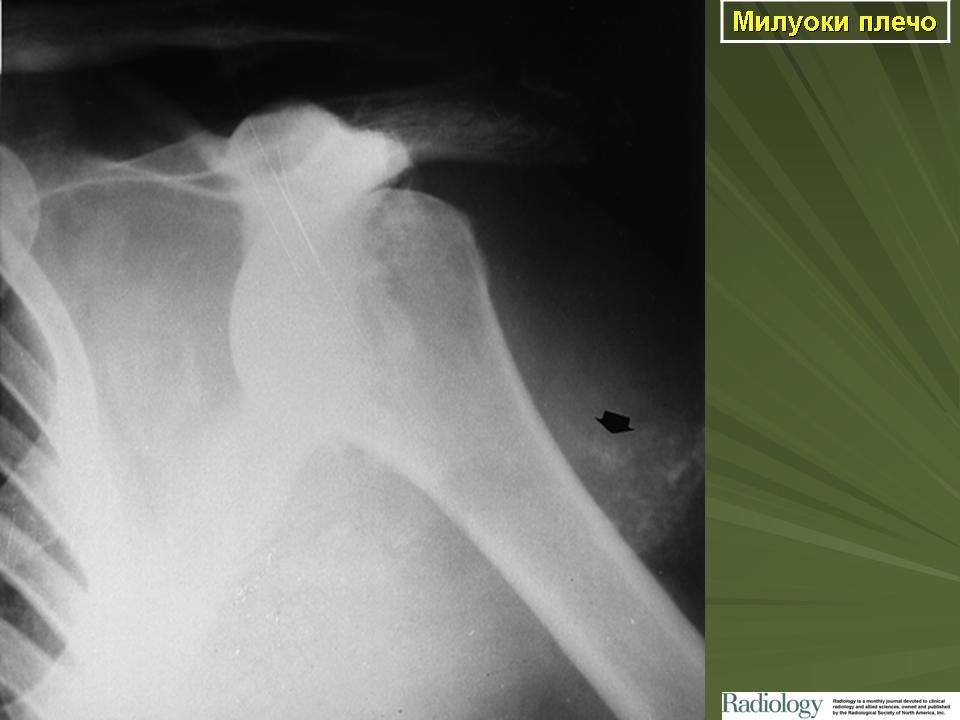

Остеоартрит - это хроническое заболевание, при котором поражаются некоторые суставы; частота этого заболевания увеличивается с возрастом. К 80-летнему возрасту практически у всех людей поражаются суставы пальцев (такие утолщения называются узелками Гебердена). Эти изменения обычно не вызывают каких-либо значимых клинических состояний. Остеоартритом поражаются, в основном, суставы, несущие нагрузку массы тела (тазобедренный, коленный, голеностопный, позвоночные суставы). Хотя плечо не несет такой нагрузки, в нем также могут развиваться артритные изменения, которые могут сопровождаться подвывихом головки плеча и выпотом, содержащим большое количество протеолитических ферментов. Это клиническое состояние называется “плечо Милуоки” и характеризуется болезненностью и ограничением подвижности плеча. Основным изменением при остеоартрите является рассасывание хряща и образование на его месте новой кости, которая обычно видна на рентгенограмме.

Обращает на себя внимание описание у лиц пожилого возраста плеча Милуоки (Milwaukee) – хондрокалциноза ПС, обусловленного отложением в суставной полости кристаллов пирофосфата кальция с последующим их фагоцитозом. Данному процессу сопутствует кальцификация мягких тканей. Заболевание характеризуется постепенным, в течение нескольких лет, развитием ограничения движений в ПС.